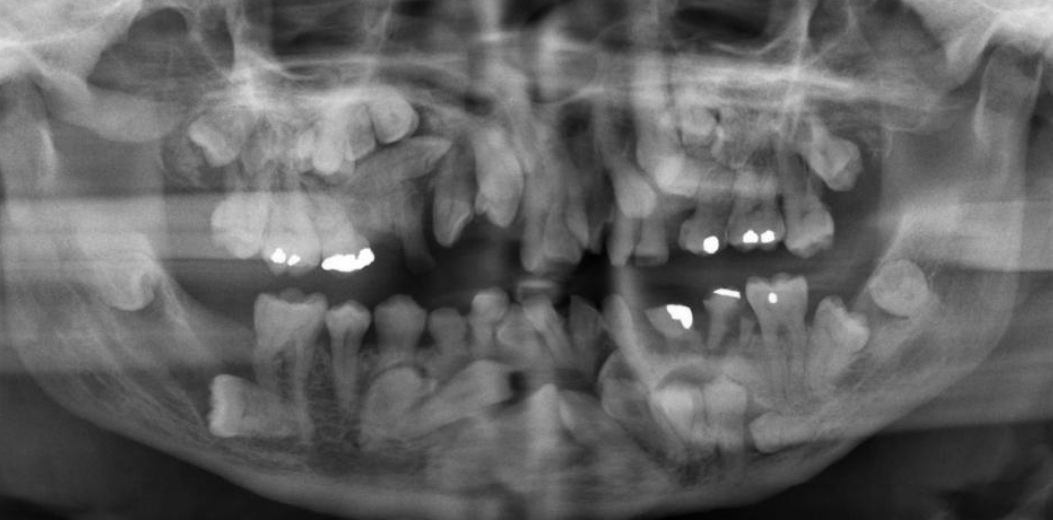

AD, AR, X-linked; both deciduous and permanent dentition are diffusely involved, affects enamel (soft, thin, easily damaged, susceptible to decay), dentin is exposed

amelogenesis imperfecta (AI)

Types of AI

hypoplastic (pitted), hypomaturation/ hypocalcification (snowcapped) AI with taurodontism

Clinical appearance of AI

yellow-brown to white pitted lesions, open bite, loss of contact